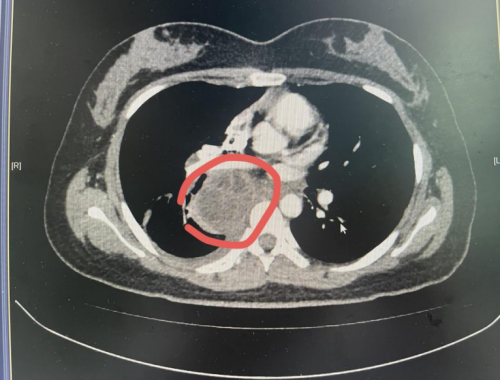

CT检查示纵隔肺门肿块大小约59×58mm

据家人回忆,近半个月来,丁香不仅出现发烧、畏寒等症状,还总说“喘不上气”。在卫生服务中心初步检查后,医生建议其来立博体育 就诊。立博体育 耐药结核中医肺病科雷丽萍医生为丁香进行了全面检查,胸部CT扫描显示,她的纵隔及肺门区存在一个肿大淋巴结伴脓肿形成,个头有鸡蛋大小。考虑到病灶位置特殊,诊断存在一定难度和风险,科室主任裴异带领团队进行多学科会诊,最终决定采用超声支气管镜下EBUS精准定位穿刺,成功获取少量脓液样本。经结核分子检测,确诊为结核分枝杆菌感染。